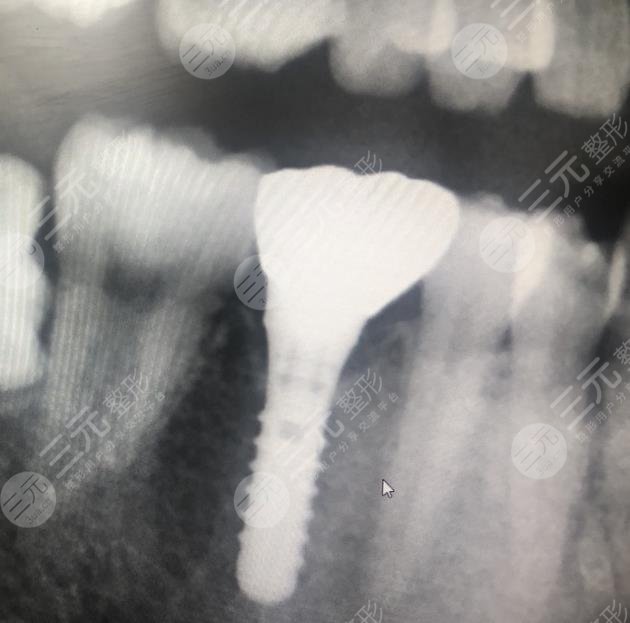

Surgical Procedure: Dental Implants

Since dental implant surgery can fill in the missing tooth and make the whole oral condition look more harmonious and natural, in order to make it more aesthetically pleasing, I agreed to this treatment. Under the guidance of a professional doctor, the oral cavity was cleaned and disinfected in a timely manner, and the missing parts were also punched, and then the implants were placed, then the abutment, and then the crown, the whole process took several months of the world, the dental implant surgery went relatively smoothly, and the whole process did not have any medical accidents, which was relatively easy for me, and the treatment was completed.

When I just finished dental implant surgery, the teeth looked more natural, although there was still a little foreign body feeling, but the overall performance was relatively good, there was no special discomfort, and there was no strong sense of stimulation.